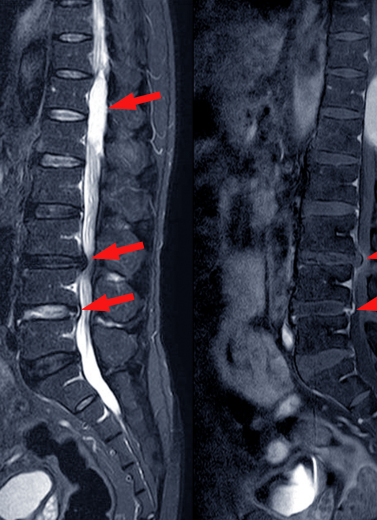

Slip Disc / Herniated Disc

Sciatica and Nerve Compression

Spinal Stenosis

Degenerative Disc Disease

Cervical & Lumbar Spondylosis